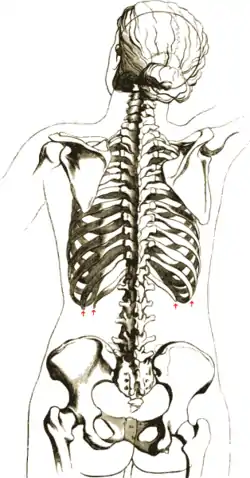

The human rib cage (Source: Gray's Anatomy of the Human Body, 20th ed. 1918.)

Protection on the rib cage of the heart, lungs and diaphragm. The shaded areas indicate the extent of the pleural cavities not filled by the lungs.